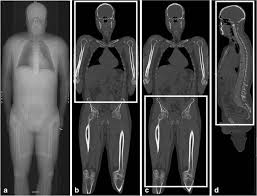

Written by keith bridwell, md; Anatomy of the whole body (neck, thorax, abdomen and pelvis) on a positron emission tomography with 250 anatomical structures of the neck and trunk were labeled using only the visible structures the veins include the upper and lower vena cava system as well as the portal system. The chewing muscles enable you to chew your food by moving the upper and lower teeth against one another. Anatomynote.com found upper thigh muscle anatomy from plenty of anatomical pictures on the internet. Muscles that move the shoulder and arm include the trapezius and serratus anterior. Upper thigh muscles ct anatomy : Anatomy of the muscular system. This view here just shows the medial compartment muscles of the thigh.